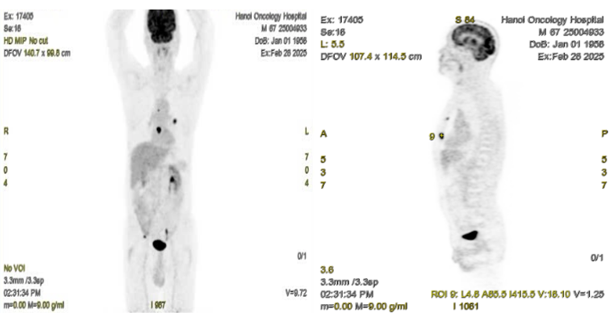

Hình 3: Hình ảnh chụp PET ở mặt phẳng coronal (bên trái) và sagittal (bên phải) thấy hình ảnh tổn thương ở phổi trái, xương ức, xương cánh chậu phải, tăng chuyển hóa FDG.

Hình 6: Hình ảnh CT cấu trúc bình thường (bên trái) và hình ảnh tăng hoạt tính phóng xạ ở xương ức trên PET/CT (vòng tròn màu đỏ) (SUVmax: 18,1)

Hình 7: Hình ảnh CT cấu trúc bình thường (bên trái) và hình ảnh tăng hoạt tính phóng xạ ở xương chậu phải trên PET/CT (vòng tròn màu đỏ) (SUVmax:7,84)